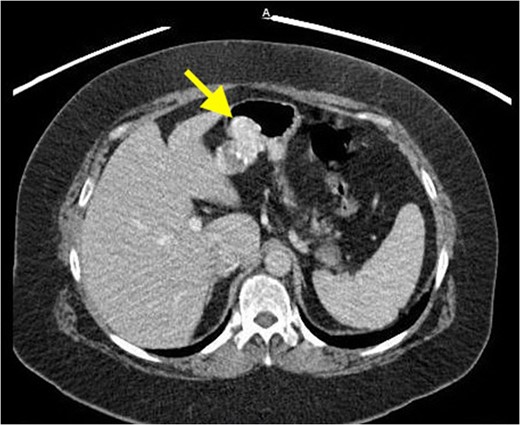

Gastric glomus tumors are rare, mesenchymal neoplasms, generally described as benign and account for nearly 1% of all gastrointestinal soft tissue tumors. The most common gastrointestinal site of involvement is the stomach, particularly the antrum. Gastric glomus tumors are submucosal tumors that lack specific clinical and endoscopic characteristics, and are often mistaken for the more common gastrointestinal stromal tumors. A 62-year-old Caucasian female presented with shortness of breath and a persistent cough. Clinical workup revealed a mass in the upper abdomen. After endoscopic ultrasound and fine needle aspiration raised concerns for cancer, the patient elected to proceed with exploratory laparotomy. A local resection was performed at the time of surgery. Pathologic and immunohistochemical findings following surgical resection were consistent with a gastric glomus tumor. Consideration of gastric glomus tumors in the differential diagnosis may optimize the chance for a more accurate preoperative diagnosis and targeted surgical intervention.

On CT, they manifest as well-circumscribed submucosal masses with homogeneous density on unenhanced study and may contain tiny flecks of calcifications [2]. However, it is important to note that imaging techniques fail to differentiate GTs from other stromal or mesenchymal lesions. The above-mentioned imaging features can also be seen with other mesenchymal tumors, such as neuroendocrine tumors, GIST, schwannoma and vascular tumors such as hemangioma and hemangiopericytoma [2]. EUS will show a hypoechoic, well-circumscribed mass located in the submucosa and/or muscularis propria [6, 7]. This is generally only advantageous in identifying the layer of tumor origin. Endoscopic biopsy is typically unhelpful in preoperative diagnosis due to the intramural nature of the tumors [2].